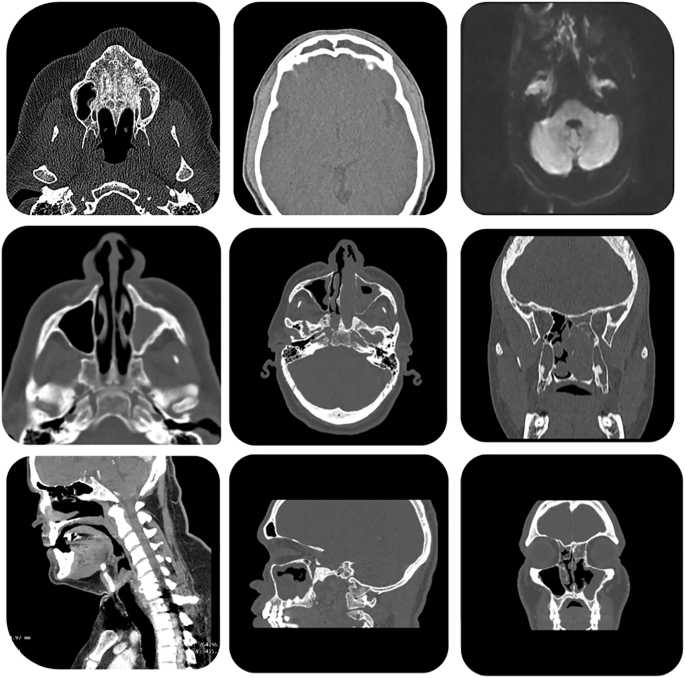

Patients with pathology-proven diagnoses of either IP or IP-SCC were retrospectively identified from 19 academic centers, totaling 958 cases (878 IP and 80 IP-SCC). From these, 41,099 CT scan slices were extracted, encompassing axial, coronal, and sagittal planes (Fig. 1). These images were labeled based on pathology results (meaning final pathology based on complete tumor resection) and used to train a two-dimensional (2D) image classification model using the Google Cloud Vertex AI AutoML platform. The dataset included a broad range of scanner types, Slice thicknesses ranged from 0.5 mm to 1 mm, with voxel sizes of approximately 0.5–0.6 mm × 0.5–0.6 mm, and imaging protocols varied, reflecting real-world heterogeneity. No image resizing or segmentation was performed to preserve original imaging characteristics and improve generalizability across diverse scan types.

Different CT scan cuts, separated into Coronal, Sagittal, and Axial views, each with different voxel dimensions and slice thicknesses, demonstrate the variety of images on which the model was both trained and validated.